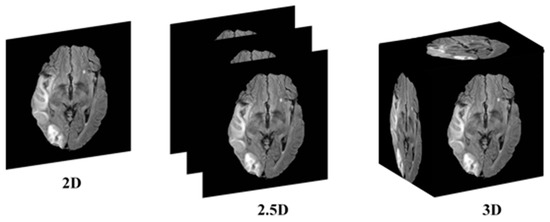

This research addresses the mentioned gaps by integrating a transformer-based backbone, specifically the Mix Vision Transformer (MiT), into the U-Net architecture. The transformer’s ability to capture long-range dependencies and global context provides a more holistic understanding of the complex spatial relationships in 2.5D MRI images, enhancing stroke lesion segmentation accuracy while maintaining computational efficiency. The 2.5D picture segmentation problem is a significant, but little-studied, segmentation task. The goal is to segment stroke lesions using a 2.5D image representation, where spatial context across adjacent slices is incorporated (Figure 1).

Figure 1. Conceptual illustration of 2D, 2.5D, and 3D segmentation inputs. In 2D segmentation, individual slices are processed independently, with no information shared across adjacent slices. In 2.5D segmentation, multiple adjacent slices (e.g., three) are stacked as input channels to capture inter-slice context, while retaining a 2D model architecture. In 3D segmentation, the entire MRI volume is processed using 3D convolutions, incorporating full volumetric context at the cost of higher computational demand.